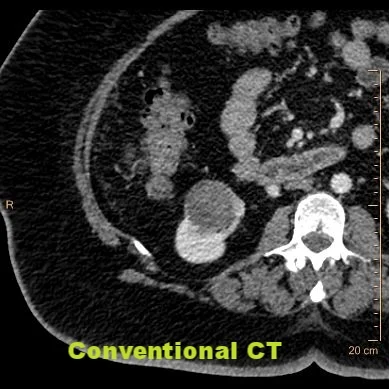

Complex kidney cyst

Hyperdense lesion in right kidney is indeterminate on routine CT.

Spectral analysis shows it is hyperdense on virtual non-contrast, and has no iodine content (on iodine map and fused image), consistent with hemorrhagic cyst.

Impression is confirmed with MRI (T2W, T1W and post-contrast subtraction image shown here).